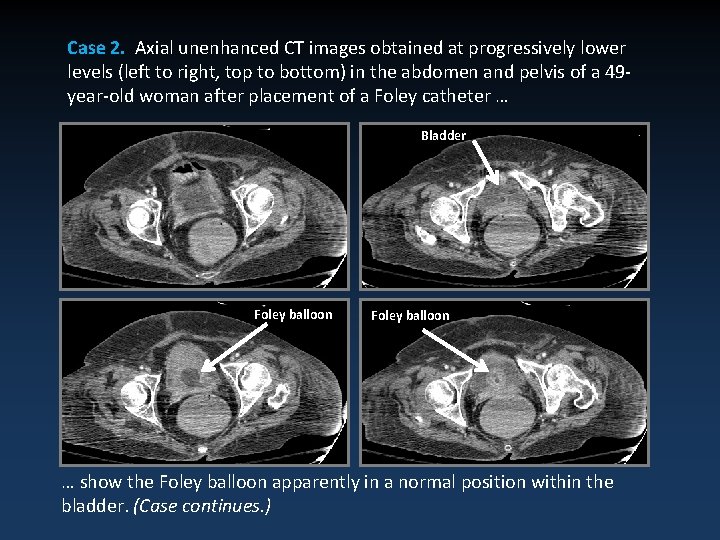

Case 2. Axial unenhanced CT images obtained at progressively lower levels (left to right, top to bottom) in the abdomen and pelvis of a 49 year-old woman after placement of a Foley catheter … Bladder Foley balloon … show the Foley balloon apparently in a normal position within the bladder. (Case continues. )